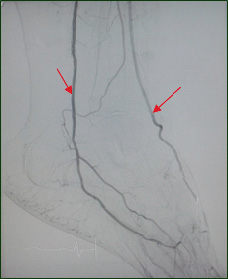

1. Fig. 1. The level of measurement of the spectral characteristics of the blood flow in the dorsal artery of the foot and posterior tibial artery (angiogram of the right foot). | |

8. Fig. 8. Angiogram of the arteries of the lower limb of a patient with diabetes mellitus and critical limb ischemia. The green arrow indicates the normal blood flow in the superficial femoral artery, the red arrows indicate the collateral vessels, the yellow arrow the blood flow in the distal segment of the artery. | |